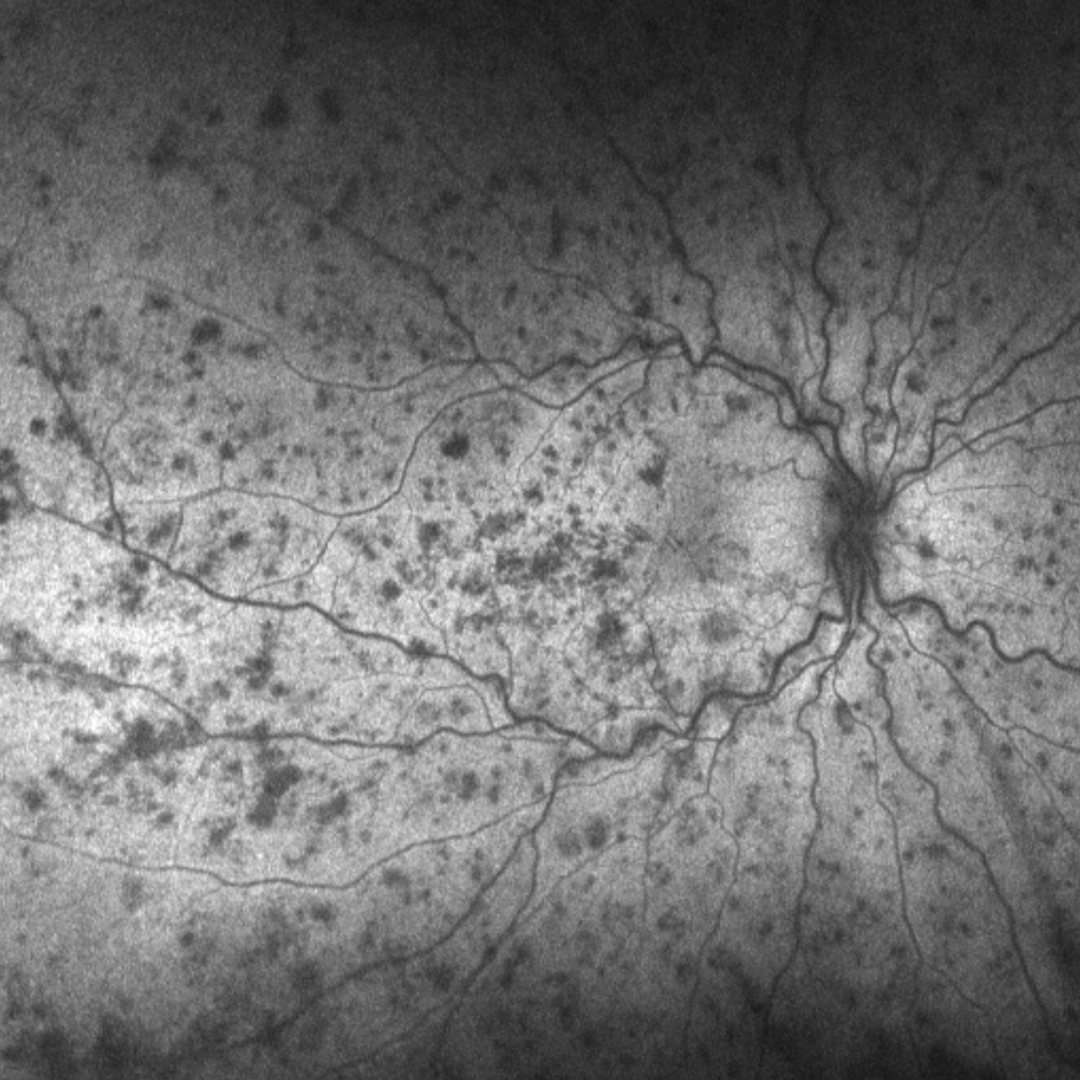

Neovascularisation can be a challenge to identify on retinal photography as the vessels as the vessels are typically very fine and thin (1). A red-free filter (or green separation widefield image) may help in identifying these vessels (2).

Retinal hypoxia and the associated release of VEGF can result in retinal or iris neovascularisation. These vessels are immature, weak and leaky.

Ischaemic retinal venous occlusions are most likely to lead to the development of neovascularisation.